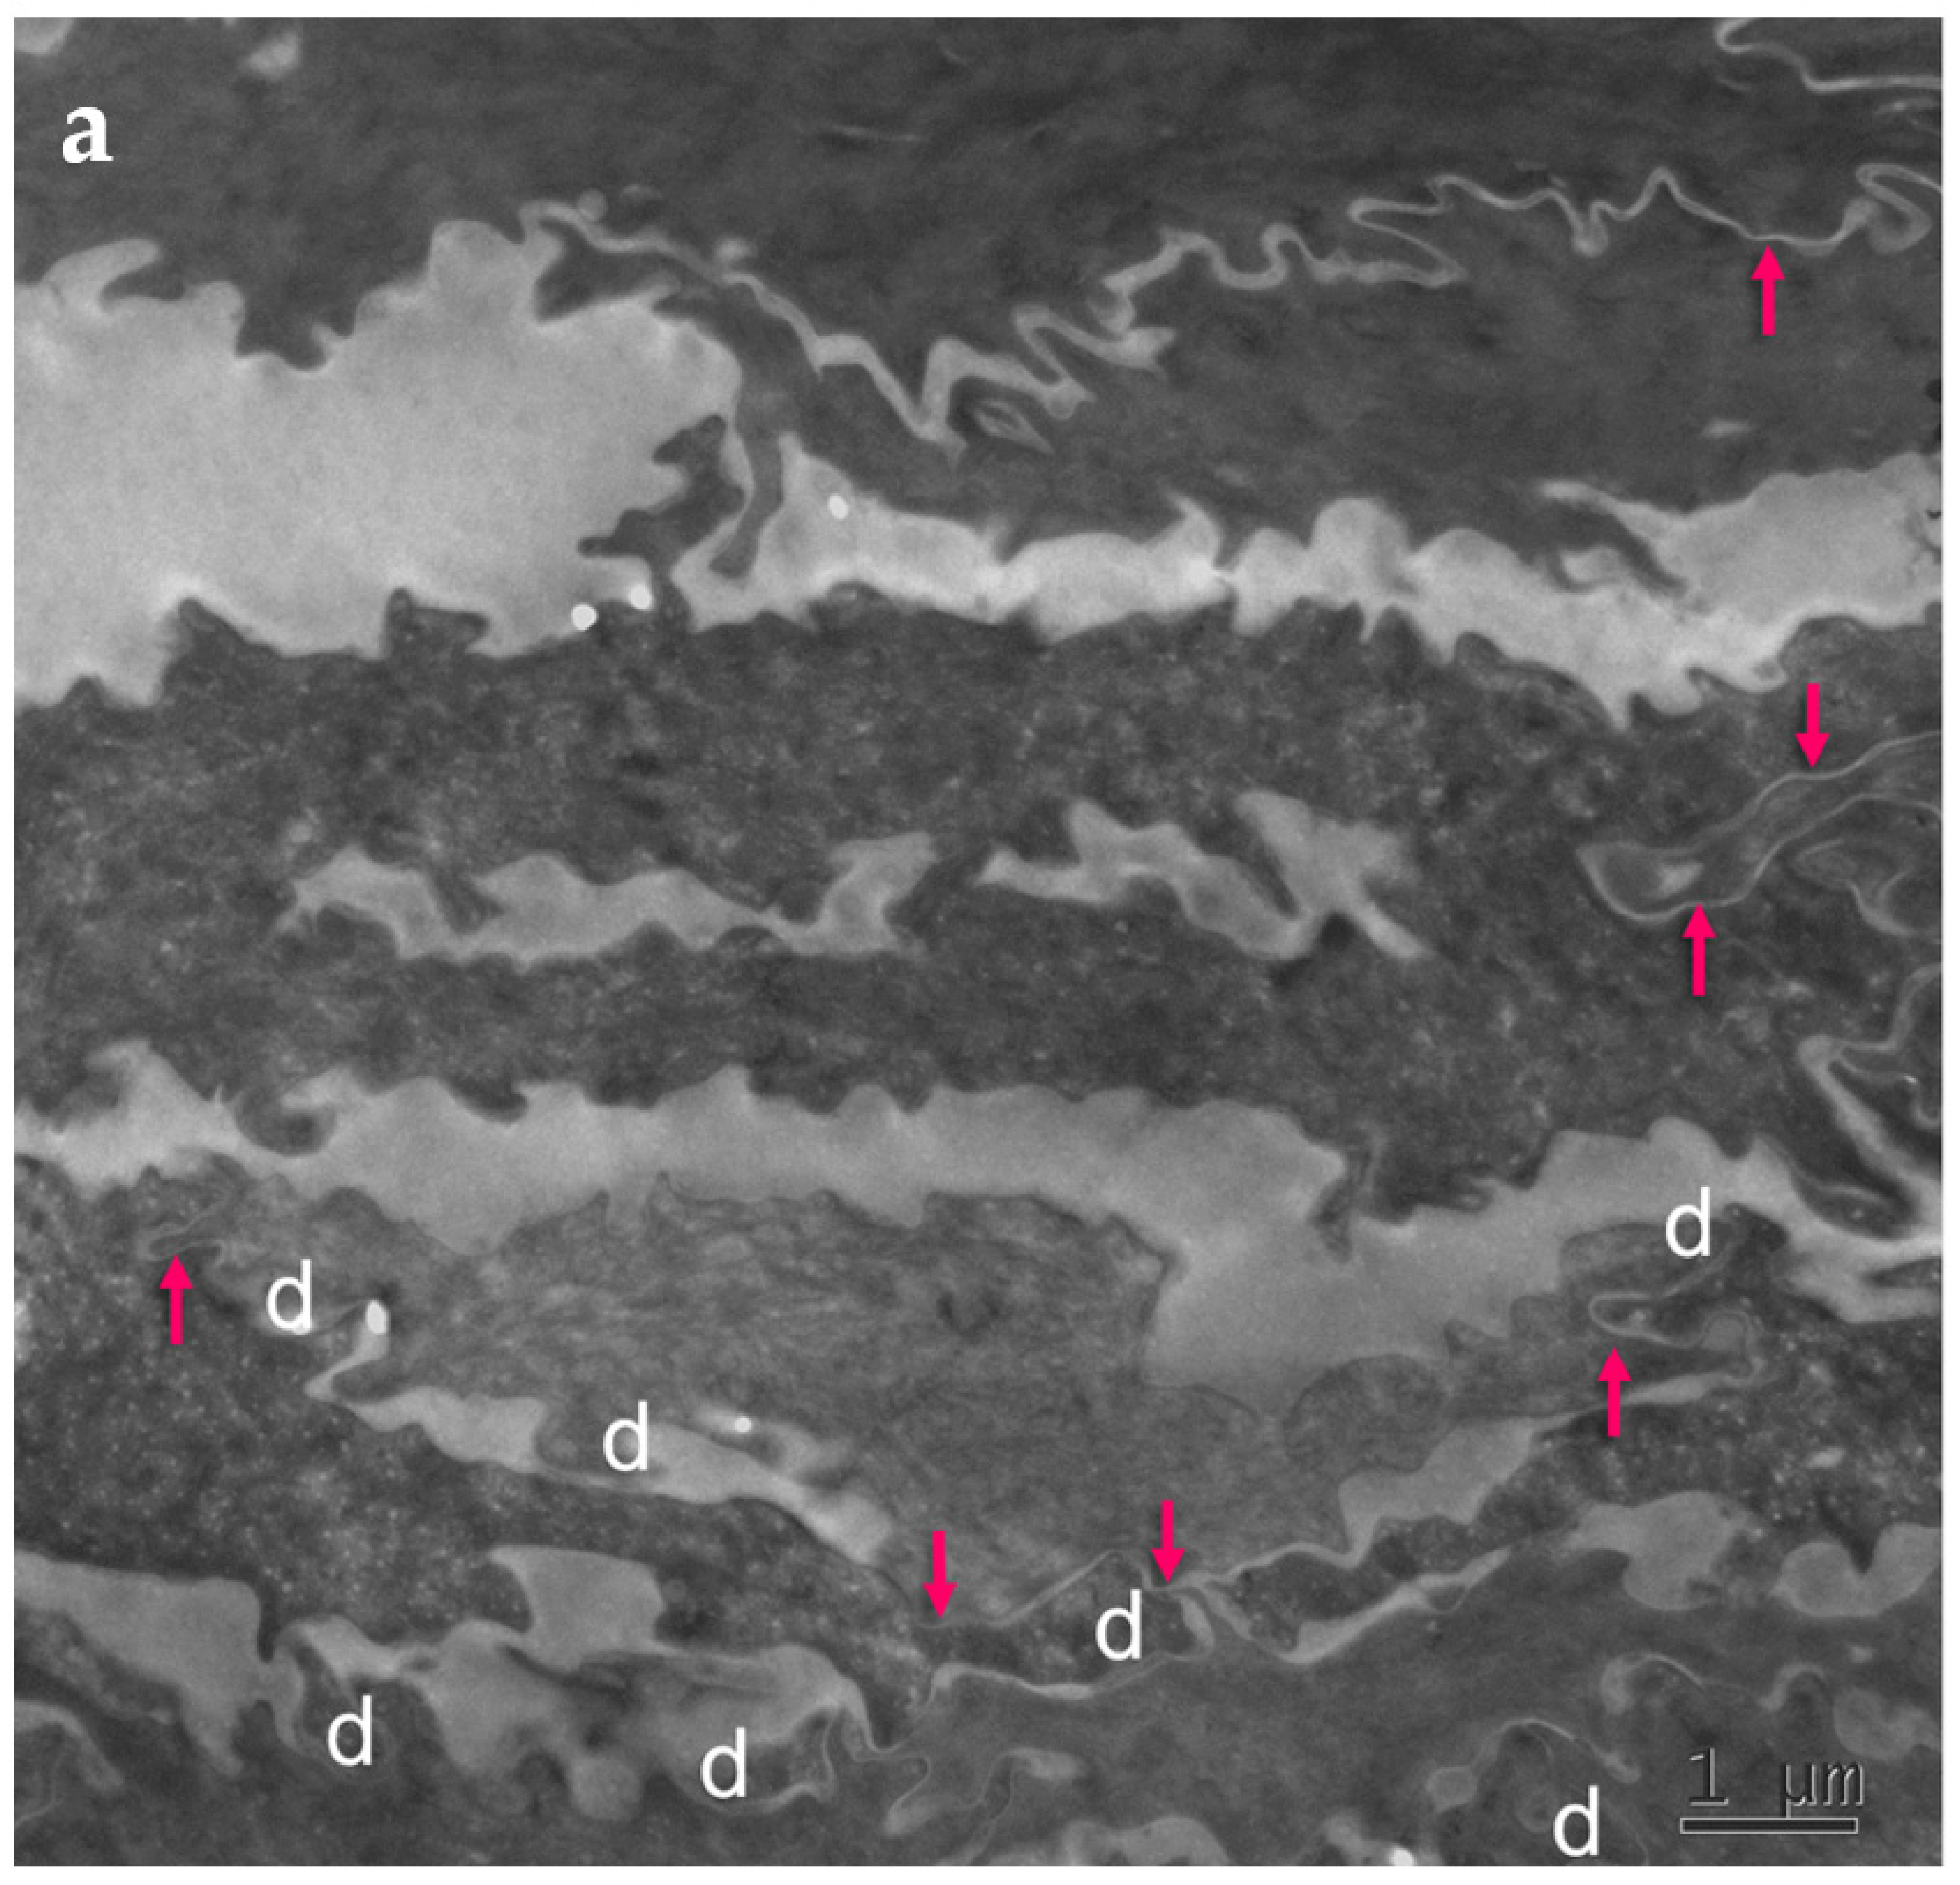

Skin biopsies and specimens of peeled-off SC were obtained from two PSD patients (Supplementary Figure S3) and examined with standard electron microscopy (Figure 4). Numerous, long TJ remnants showing “fused” lipid envelope morphology were present in PSD and contributed to the lateral cohesion within the SC. They also seemed to promote formation of highly developed interdigitations, which constituted yet another factor rescuing SC cohesiveness despite degradation of “central” corneodesmosomes situated between consecutive layers of corneocytes.

Figure 4.

Ultrastructural features observed in the SC of PSD include paucity of corneodesmosomes (d) that rapidly disappear from the lower parts of the horny layer, as seen in (a), and upregulation of expression of TJ-derived intercorneocyte “fusions” (arrows). (b) In the upper SC, the remaining corneodesmosomes (d) are often found in the proximity of the TJ-derived riveting structures (arrows). Bars = 1 µm in (a); 0.5 µm in (b).

The cell–cell fusions of lipid envelopes in the upper part of the lateral intercorneocyte contacts, which have been shown to result from the persistence of TJ structures, were quantified and the results compared with the situation in 35 normal controls (Table 4).

Table 4.

Fraction of the apical-lateral contacts between corneocytes showing “fused” morphology in the SC of PSD. NHS = normal human skin.

Upregulation of the TJ-derived corneocyte envelope fusions in PSD may represent a compensatory phenomenon in face of corneodesmosome fragility. It may contribute to cohesion in the upper SC directly, through enhanced cell–cell adhesion, and indirectly, by hindering access of extracellular hydrolytic enzymes to corneodesmosomes.